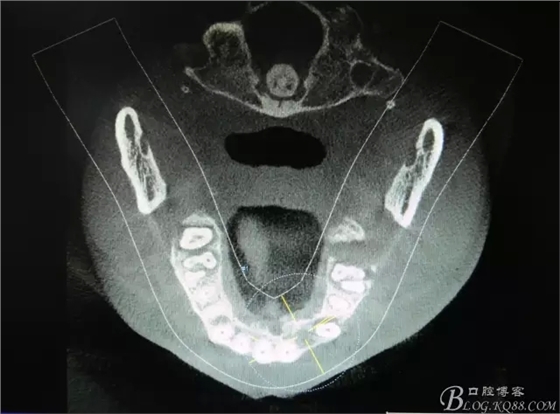

圖2.CBCT的三維成像及縱剖面、水平面影像